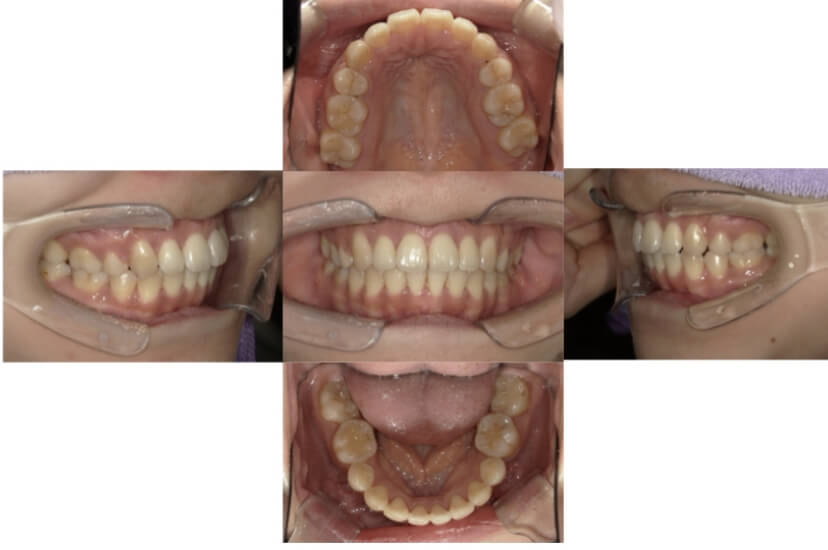

BEFORE

AFTER

上下顎叢生、反対咬合(上下の前歯のガタガタ、若干受け口)のケースです。

装置はラビアル(上下表側)で、上下顎の小臼歯を4本抜歯を行っています。抜歯したスペースを使って、上下の叢生改善と前歯の受け口の改善を行っています。

主訴 前歯のガタガタを治したい。

年齢・性別 45歳 女性

お住まいの地域 神奈川県川崎市

治療方針 抜歯スペースを利用して上前歯の叢生(ガタガタ)の改善と受け口の改善

抜歯部位 上顎左右第一小臼歯、下顎左右第二小臼歯

使用装置 ラビアル(上下表側)、顎間ゴム

治療期間 2年6か月

治療回数 20回

リテーナー クリアリテーナー